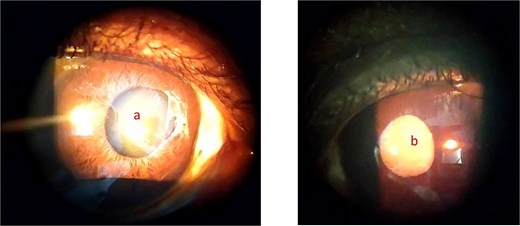

On ophthalmic examination with slitlamp biomicroscope the patient had bilateral temporal iris atrophy with the pupillary margin in the right eye having a torn iris sphincter and mid dilated as well (Fig. 1). The lens in both eyes were clear using Lens Opacities Classification System III (LOCS III) and as well as the vitreous in the right eye. In the right eye fundus, there were drusens at the macular and in the peripheral retina there were black sunbursts lesions (Fig. 2a and b). There was vitreous haemorrhage and no retinal detachment in the left eye, and this obscured the view of the fundus (Fig. 3).

Showing anterior segment photography of right eye (a) and left eye (b) respectively with iris atrophy temporally and torn iris sphincters.

On ophthalmic examination with slitlamp biomicroscope the patient had iris atrophy with torn iris sphincter nasally in the right eye and mid dilated as well. The lens in the right eye was clear using LOCS III grading (Fig. 4a). The left eye had a complicated cataract, and this obscured the view of the fundus (Fig. 4b). There were vitreous tractions at the macular (Fig. 5) and black sunbursts lesions in the peripheral retina in the right eye during funduscopy.

Showing anterior segment photograph of the right eye with iris atrophy (a) and complicated cataract in the left eye (b).